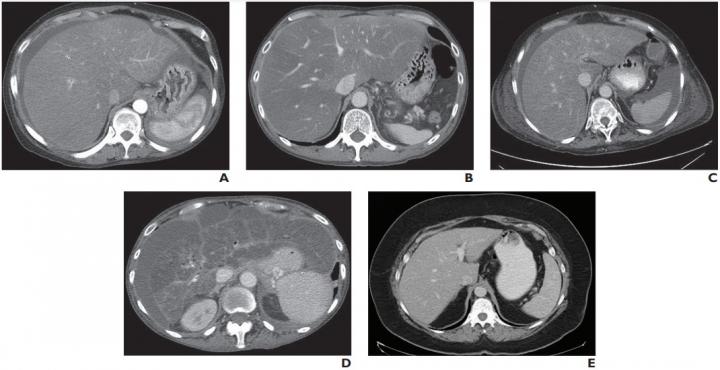

image: A and B, True-positive assessments in 58-year-old woman (A) and 52-year-old man (B) with high-risk NAFLD and associated NASH. CT images show hepatic enlargement, heterogeneously low-attenuation hepatic parenchyma, and surrounding ascites. Readers correctly identified NASH according to these imaging features. Readers also correctly identified fibrosis stage F3.

C and D, False-positive assessments in 73-year-old woman (C) and 61-year-old woman (D) with high-risk NAFLD but without pathologic evidence of NASH. CT images show findings similar to A and B. Readers incorrectly identified NASH because of these imaging findings but correctly identified fibrosis stages F3 (C) and F4 (D).

E, False-negative assessment in 56-year-old woman. CT image shows liver is not enlarged, heterogeneous, or low in attenuation, and ascites is not present. Both readers interpreted image as not showing findings indicative of NASH. However, NASH was diagnosed from surgical pathology.